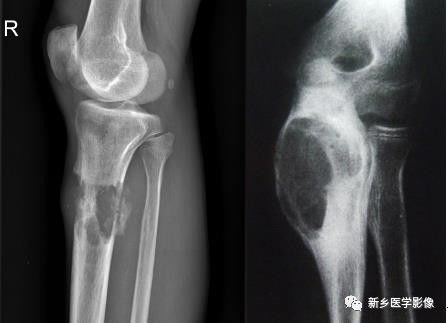

骨质破坏X线图像

a. 膝部X线侧位片示胫骨上段不规则溶骨性破坏,局部见软策划肿块。b.肘关节正位片示尺骨上段膨胀性骨质破坏,边缘骨质硬化,无软策划肿。

骨质破坏见于炎症、肉芽肿、肿瘤或肿瘤样病变。由于病变的性质、发展的快慢和邻近骨质的反应性改变不同,不同病因导致的骨质破坏在X线表现上具有一定的特点。如在炎症的急性期或恶性肿瘤,骨质破坏常较迅速,轮廓多不规则,边界模糊,可称为溶骨性破坏。而炎症的慢性期或良性骨肿瘤,则骨质破坏进展较缓慢,边界清楚,在骨破坏区边缘往往可见一致密的骨质增生硬化带围绕;如导致骨轮廓的膨胀,可称为膨胀性骨破坏。